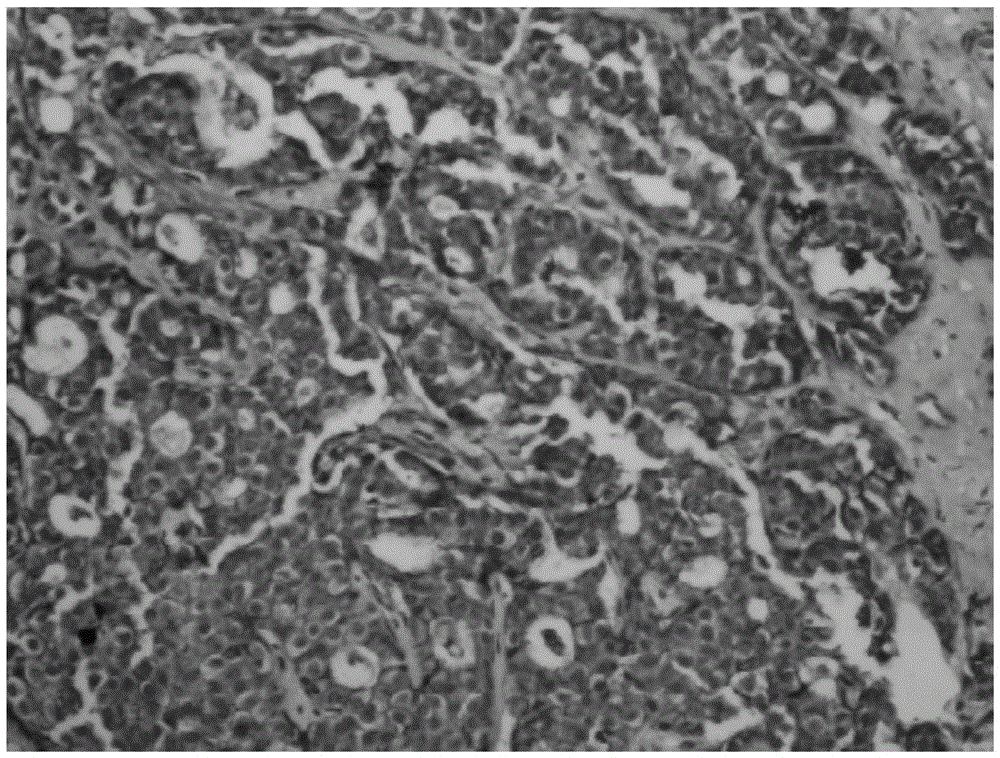

一种多聚体酶-抗体及其制备方法